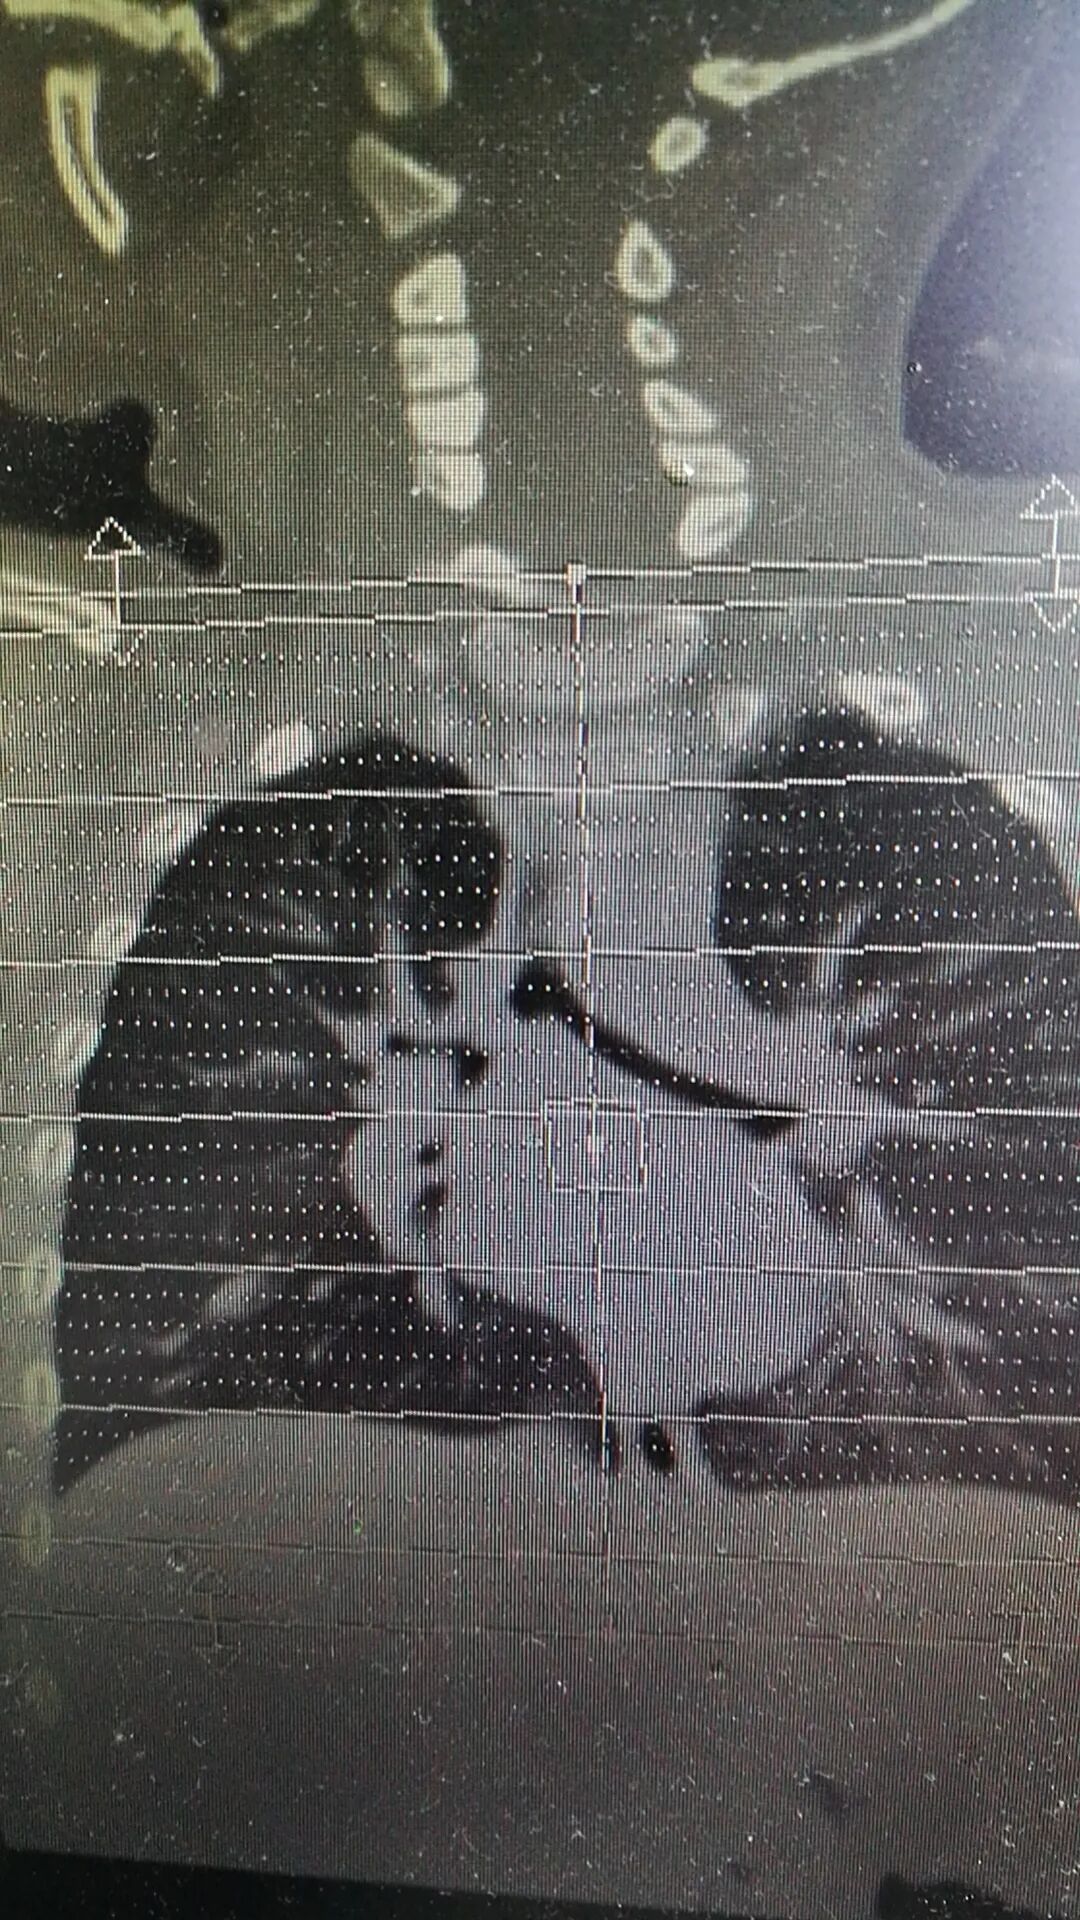

姜毅教授带领团队分析,扬扬极有可能是支气管异物导致的症状。虽然家属一再否认孩子有“呛咳史”,但姜毅教授反复规劝家长,尽快为孩子进行CT胸部平扫+支气管成像检查。

2日中午医院放射科紧急回报危急值“考虑右侧主支气管腔内异物”,证实了医生的判断。